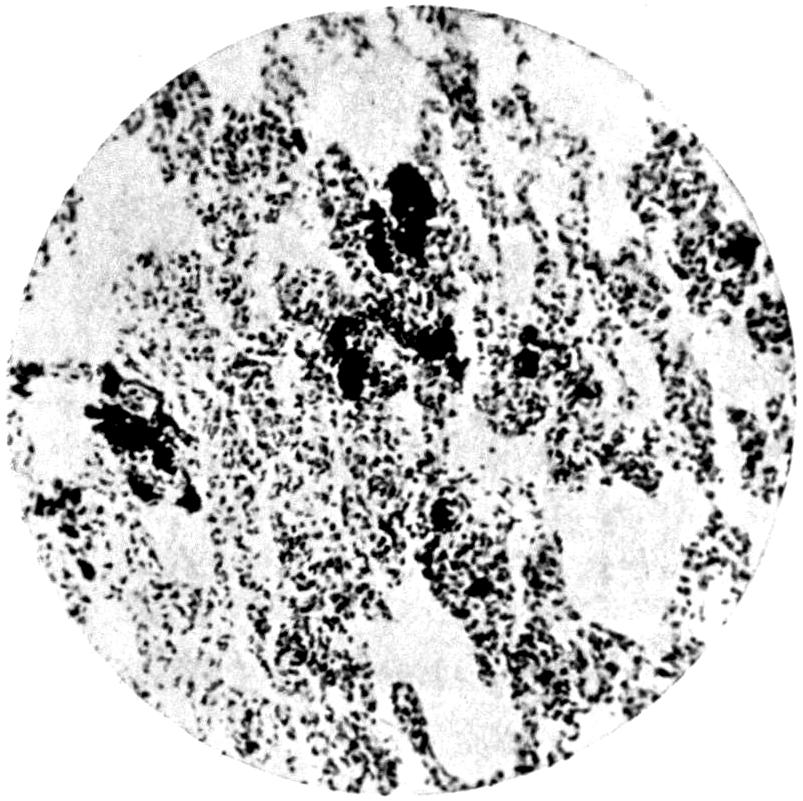

Plate II. 93